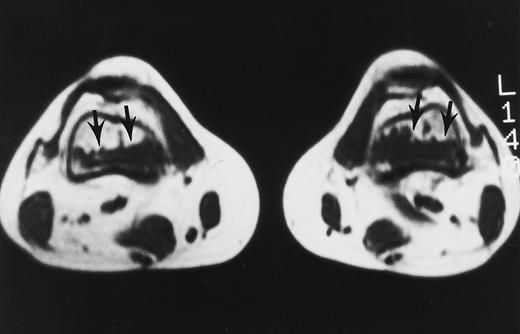

A 32-year-old woman with AML and biopsy-proven fibrosis in the marrow. T1-weighted (500/10, TR/TE) axial MR image of the distal thighs shows foci of fibrosis (arrows) with dark signal. On T2-weighted MR images (not shown), the signal of the lesions did not change.

In myelofibrosis, the bone marrow may be hypercellular or depleted of all hematopoietic elements. Fibrotic marrow is visualized as areas of markedly low signal on all MR sequences (Fig 15).74 75 Unless the characteristic appearance of fibrotic marrow is seen, myelofibrosis cannot be distinguished from other hematologic malignancies with MR images alone.